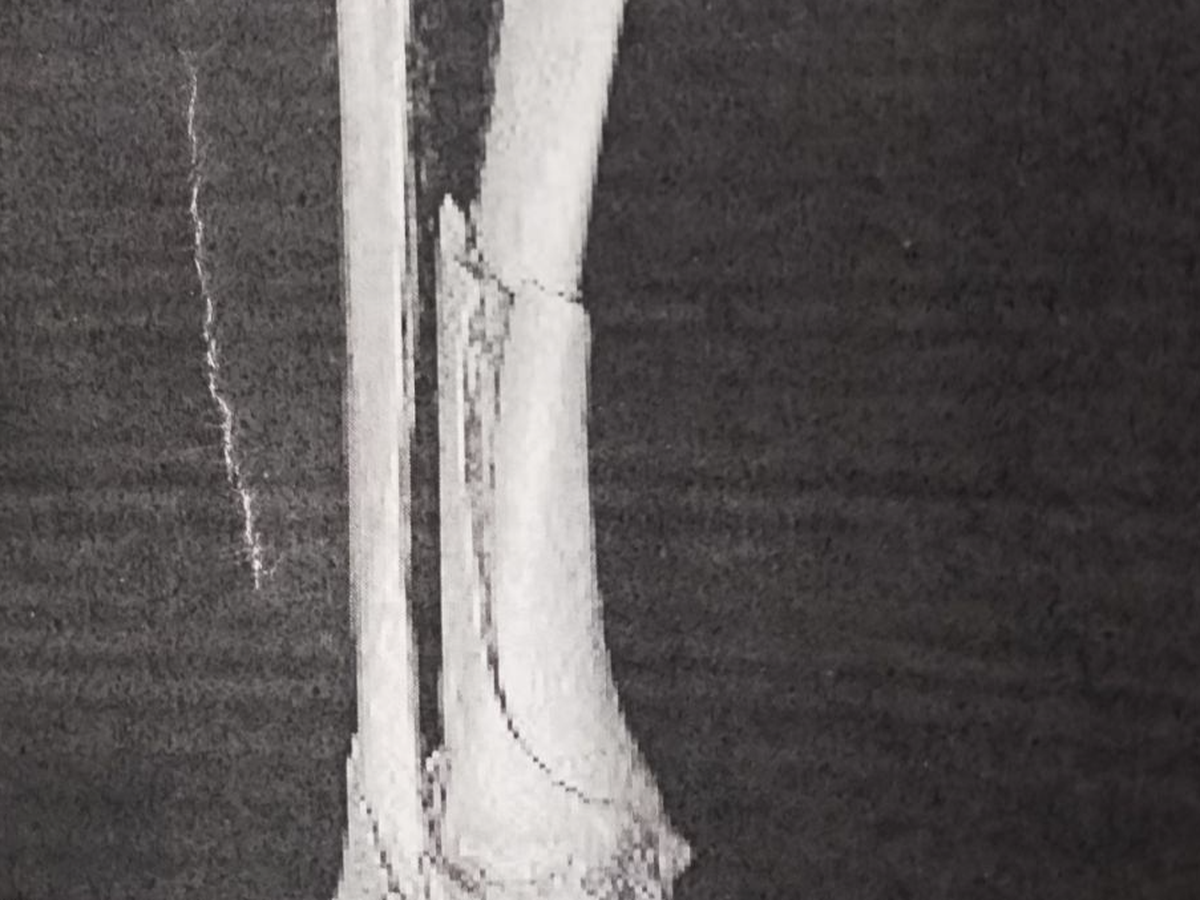

Hi, my name is Luke, and I am setting up this fundraiser for our good friend, Karl Geiger. Karl is the quintessential small-town mechanic, he knows everyone by name, loves to chat and we are lucky enough to have him in our town. He has served in the local EMS system in years past and has been an integral part of the Sierra Madre Winter Carnival for several years. He recently broke both his tibia and fibula in his right leg while doing what he loves most...snowmobiling. Because Karl owns and operates his business solo, he is without medical insurance and has no current income. Karl's mounting medical debt is stressful and not conducive to proper healing. He has already undergone one surgery, has at least one more coming up and, as we all know, out of pocket medical is incredibly expensive. Any amount is so appreciated by someone who is willing to help out others like Karl is. Let's help our friend, who has been an amazing part of our community for years!